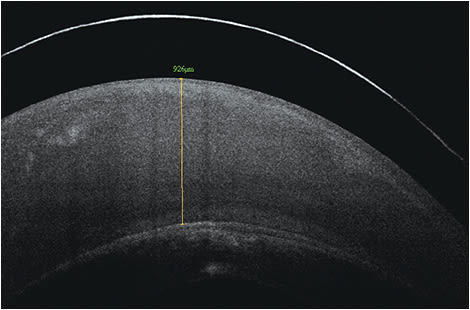

Fitting scleral lenses is typically done by selecting the best sagittal height match between the cornea and the contact lens. The desired central vault over the corneal surface varies according to lens design and the clinicians’ desired fitting philosophy for each individual patient. Typical values will range from about 150 to 400 microns. Figure 1 shows an example of excessive sagittal vault. Figure 2 shows an example of insufficient vault. And, Figure 3 shows an example of a desired amount of vault. Note: Scleral lenses settle into the bulbar conjunctiva over time following application. As such, central vault values can decrease by as much as 100 to 200 microns over a few hours after application.

Figure 1. Sagittal height of 850 to 1,000 μm = excessive vault.

Alternatively, anterior segment optical coherence tomography (AS-OCT) can be used to precisely measure scleral lens vaulting at any point beneath the scleral lens and can also be used to evaluate the landing zone over the bulbar conjunctiva/sclera. You can determine the appropriate vault over the cornea by selecting the appropriate sag of the contact lens and measuring the post-lens tear film.